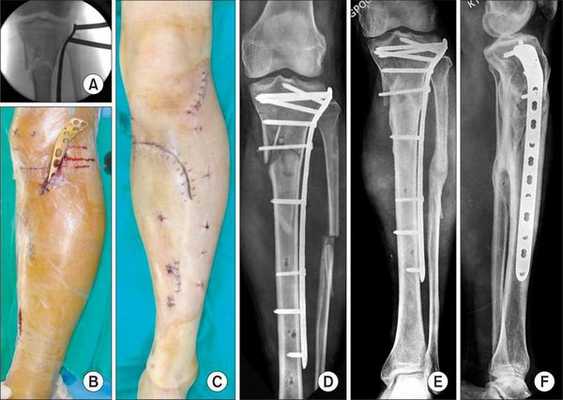

Лечение

При поступлении проведена анестезия места перелома раствором новокаина 0,5 % — 40,0 мл. Выполнена попытка одномоментной закрытой ручной репозиции перелома внутренней лодыжки и устранения подвывиха стопы. После этого больной госпитализирован в профильное отделение для определения дальнейшей тактики лечения.

После обследования и уменьшения отёка мягких тканей на четвёртые сутки с момента травмы больному проведено оперативное вмешательство. Под спинномозговой анестезией выполнена открытая репозиция перелома внутренней лодыжки правой голени спицами и стягивающей проволочной петлёй, фиксация дистального межберцового синдесмоза стягивающей петлёй с упорными металлическими площадками.

Ранний послеоперационный период протекал без осложнений. На третьи сутки после операции конечность фиксирована гипсовой повязкой от нижней трети правого бедра до плюснефаланговых суставов. Пациент активизирован с опорой на костыли без нагрузки на правую нижнюю конечность. Выписан на амбулаторное долечивание под наблюдение районного травмпункта.